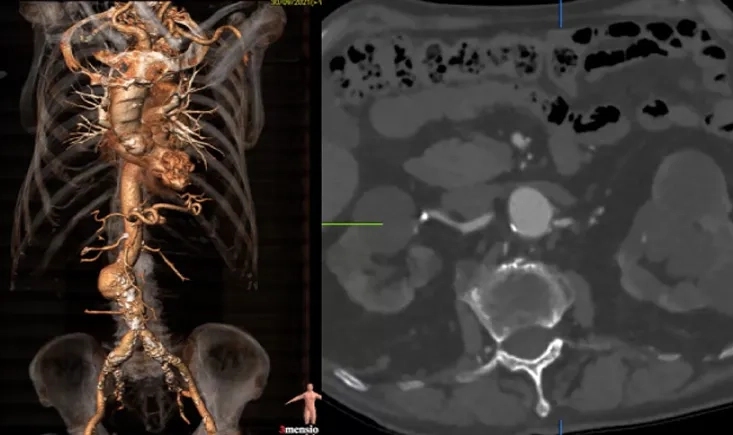

An 80-year-old patient faces a recurrent type II endoleak after EVAR, with his aneurysm sac continuing to g…